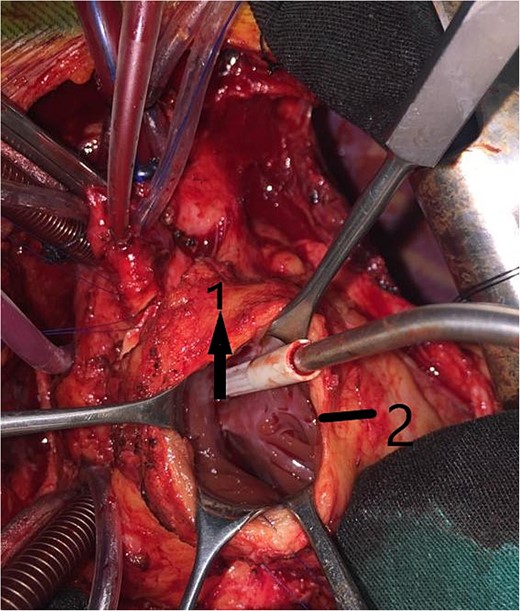

An 11-year-old girl was referred to our hospital with a main complaint of progressive exertional dyspnea. She had undergone surgical repair of SAS 6 years ago. Transthoracic echocardiogram (TTE) revealed the following findings: severe left ventricular hypertrophy, tunnel-like fibromembranous subaortic stenosis with a length of 10 mm, a peak gradient (PG) across the LVOT of 170 mmHg, and mild aortic regurgitation. Based on these findings, the patient was scheduled for elective surgical repair with a possible indication for MKO. The operation was performed via median sternotomy with great caution to avoid inadvertent rupture of any cardiac cavity due to heavy adhesions from the previous operation. The aorta was cannulated just below the takeoff of the innominate artery. Bicaval cannulation was performed to provide a bloodless field. Aortic cross-clamping was applied, and antegrade cold blood cardioplegic solution was administered via a catheter placed in the ascending aorta. The ascending aorta was opened transversely 1 cm above the sinotubular junction (Fig. 1). The aortic valve leaflets were examined carefully to confirm that the aortic valve could be preserved. LVOT was examined thoroughly, and it was clear that the stenosis in the subaortic area was so complex that simple resection through the aortic valve orifice would not be sufficient. The right ventricular outflow tract was opened transversely below the pulmonary valve. The conal papillary muscle was identified (Fig. 2). A right-angle instrument was introduced through the aortic orifice into the interventricular septum, and the tip of the instrument was used to perforate the conal septum to the left of the conal papillary muscle to prevent damage to the conduction system; the septal incision was completed with great caution to avoid damage to the aortic cusps and to extend the incision downward as necessary to completely relieve the stenotic subaortic area (Fig. 3). Interrupted 5/0 Prolene sutures were placed circumferentially around the septal incision to close the interventricular septal defect using a bovine pericardial patch to provide adequate widening of LVOT (Fig. 4). The right ventriculotomy was closed with a second bovine pericardial patch to avoid any possible obstruction of the right ventricular outflow tract (Fig. 5). The remainder of the operation was completed uneventfully. After 6 hours of mechanical ventilation, the patient was extubated, and she convalesced well postoperatively. TTE showed excellent results of the operation with PG across LVOT of 20 mmHg. On 1 year follow-up, the patient was asymptomatic and in very good general condition, and TTE findings confirmed the excellent result.

Intraoperative image showing the interrupted sutures placed around the septal incision.